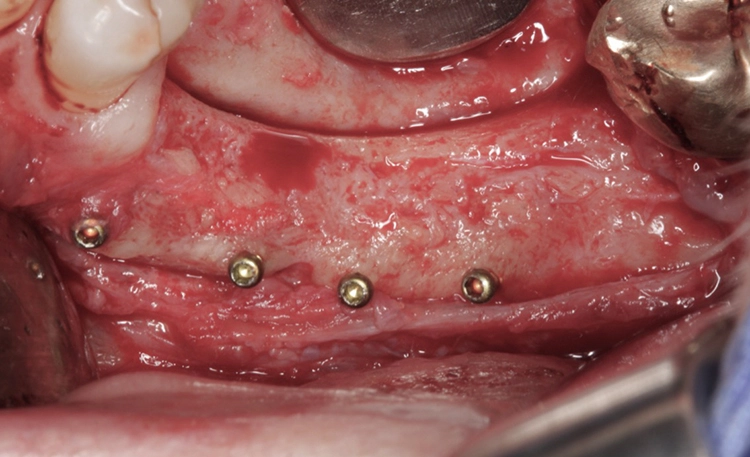

Die Wiedereröffnung des Operationsgebietes erfolgte nach vier Monaten. Länger sollte nicht mit dem Re-entry gewartet werden. Es zeigte sich, dass nur wenig keratinisierte Schleimhaut am Tag der Freilegungsoperation vorhanden war. Daher wurde sich für die sog. Kazanjian Vestibulumplastik entschieden, mit der wieder ein Vestibulum und damit auch fixierte Schleimhaut im periimplantären Bereich hergestellt werden kann (Abb. 10 und 11).

Die Kazanjian Vestibulumplastik startet mit einer halbmondförmigen Inzision ins Vestibulum, wobei ein Mukosalappen präpariert wird. In diesem ersten Schritt wird der Muskel von der Mukosa separiert. An der mukogingivalen Grenze erfolgt die Durchtrennung des Periosts, d. h. ab hier wird ein Mukoperiostlappen gebildet. Im letzten Schritt werden die Muskelfasern vom Periost separiert. Der Knochen kann nun freigelegt werden und die Implantatinsertion erfolgen.

Es zeigte sich eine komplette Verknöcherung des Augmentats und keine Resorptionen im Bereich der Fixationsschrauben (Abb. 12) und es erfolgt die Entfernung der Osteosyntheseschrauben und die Implantation von zwei Implantaten (Abb. 13 und 14). Nun erfolgt das Vernähen des Mukosalappens apikal am Periost im Rahmen der Kazanjian Vestibulumplastik, um das Vestibulum wieder zu rekonstruieren (Abb. 15). Die offene Wundfläche Richtung Wange wird der sekundären Wundgranulation überlassen.